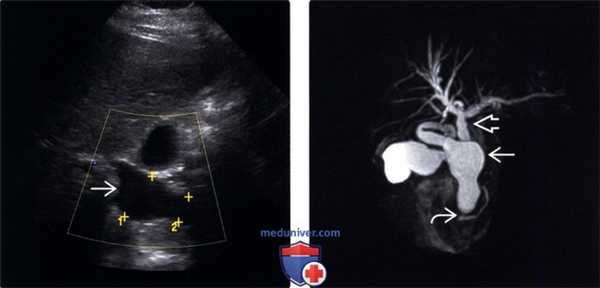

(Левый) При ультразвуковом исследовании в черно-белом режиме определяется значительное веретеновидное расширение общего желчного протока, что соответствует кисте холедоха I типа.

(Правый) При МР холанги-опанкреатографии у этого же па -циента подтверждаются выраженная дилатация общего протока и небольшое вторичное расширение внутрипеченочного протока, что соответствует кисте холедоха I типа. Обратите внимание на аномальное слияние протока поджелудочной железы и общего желчного протока — аномальное панкреатобилиарное соустье.